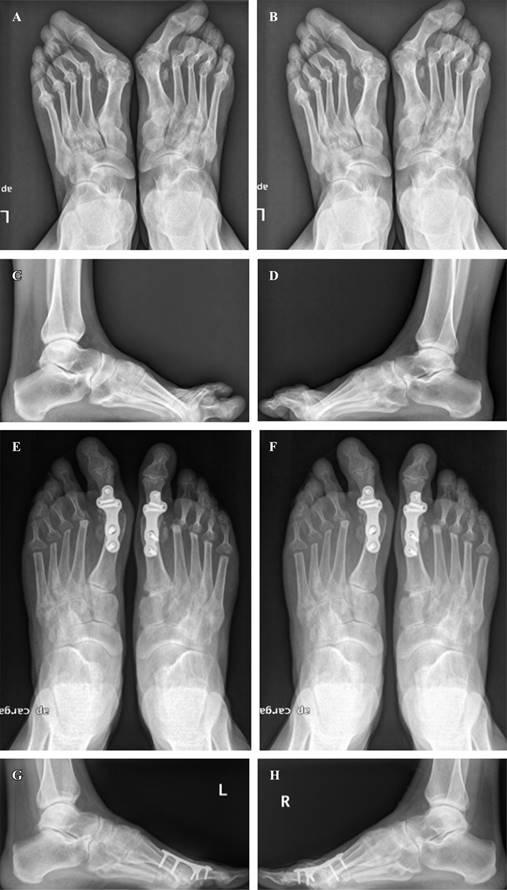

Desde el punto de vista radiográfico, el valor promedio del AHV en la última visita de seguimiento fue 21.4 ± 10.6 grados, significativamente más bajo que el valor medio preoperatorio de 49.7 ± 15.2 grados (p = 0.0001). El valor promedio de IMA también mejoró significativamente, desde 14.9 ± 3.6 grados preoperatorios a 8.4 ± 2.5 grados en promedio en la última visita de seguimiento (p = 0.001) (Figura 2).

Figura 2: Radiografías anteroposteriores y laterales en bipedestación, pre y postoperatorias, en el seguimiento final de un paciente intervenido en ambos pies (A-H). Las radiografías preoperatorias muestran deformidad tipo hallux valgus grave y destrucción/luxación de todas las articulaciones metatarsofalángicas menores (A-D). Se realizó artrodesis de la primera articulación metatarsofalángica combinada con la artroplastía de resección de las articulaciones metatarsofalángicas menores (E-H).